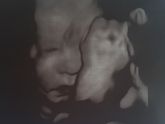

Девочки хотела у Вас узнать про покрытием гелем, хотела в понедельник сделать френч белый классический на руках и на ногах- можно ли с такими ноготками на ПКС, просто говорят что нужно вообще без лака и тем более без геля... как вы думаете?